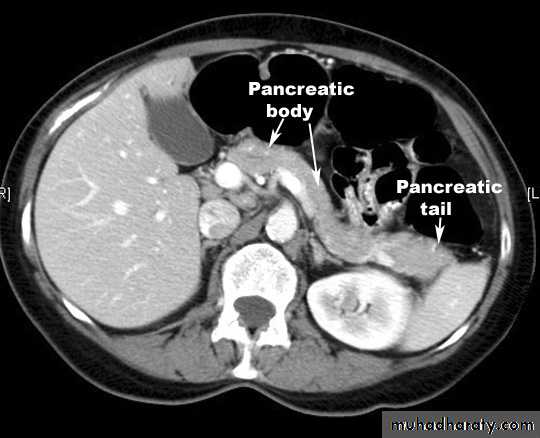

Splenic injurypancreas

Acute Pancreatitis